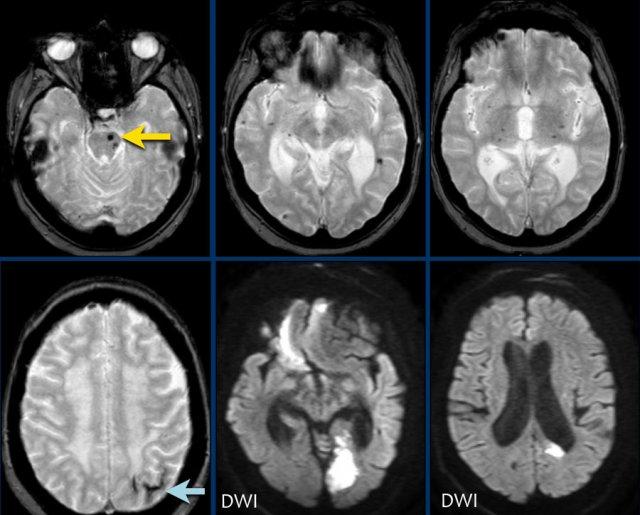

Bệnh nhân CAA này có xuất huyết vi thể, nhiễm sắt bề mặt và nhiều ổ nhồi máu.

Lưu ý ổ xuất huyết ở cầu não (mũi tên vàng).

Có hình ảnh nhiễm sắt bề mặt ở vùng chẩm trái.

Chuỗi xung DWI cho thấy ổ nhồi máu ở thùy chẩm trái và thùy trán phải (kèm theo một số xảo ảnh).